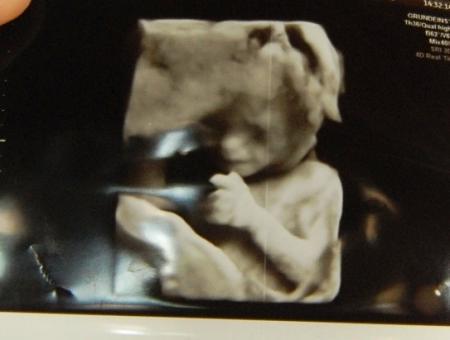

und noch ein Bildchen, man kann schon richtig viel erkennen... jetzt fehlt nur noch ein Name..

Ein schönes Bild! Ich staune immer, wie viel man bei euch auf den Bildern erkennen kann. Die sind so schön deutlich. Meine Bildchen sind irgendwie immer so verschwommen...

Was für ein schönes Bild Beim Ultraschall selbst können wir auch alles super erkennen, aber auf den ausgedruckten Bildern ist es schon wieder schwer zu erkennen. Aber die FA macht auch kein 3D Ultraschall. Nur normaler. Ich freu mich für dich, dass alles gut is!!!